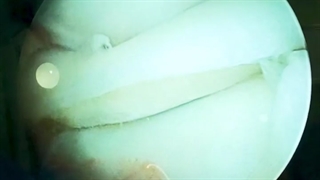

قفل شدن زانو و پارگی منیسک زانو

دکتر رضا شیروانی بختیاری متخصص ارتوپدی با ارائه خدمات جراحی های تعویض مفصل زانو و جراحی آرتروسکوپی زانو و درمان آسیب های ورزشی می پردازد . برای مشاوره و تعیین وقت قبلی با شماره های ۰۲۱۲۶۷۴۰۵۸۰ – ۰۲۱۲۲۰۷۳۱۲۵ تماس بگیرید یا به آدرس اینستاگرام (https://www.instagram.com/dr.reza.shirvani.bakhtiyari/) یا سایت (http://doctor-shirvani.com) مراجعه کنید .